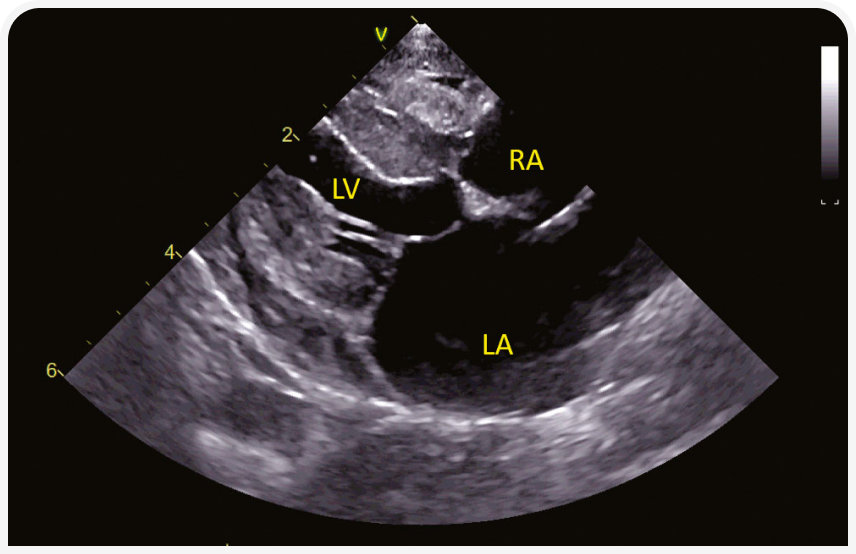

Плевральный выпот при застойной сердечной недостаточности обычно оказывается несколько модифицированным транссудатом, но может быть и хилезным. При проведении T-POCUS необходимо субъективно определить размер левого предсердия (ЛП); если оно представляется нормальным, связь одышки с ЗСН маловероятна. Наличие В-линий (гиперэхогенные радиальные линии в легочном поле, указывающие на комбинированное заполнение альвеол жидкостью и воздухом) в сочетании с увеличением ЛП, скорее всего, указывает на кардиогенный отек легких (Рисунок 1). Декомпенсация с развитием молниеносного отека легких может быть спровоцирована стрессовым фактором, анестезией, внутривенным введением жидкости, введением стероидов. Декомпенсация существующей кардиомиопатии также может быть связана с сопутствующим заболеванием, особенно если оно приводит к перегрузке объемом или к состояниям с высоким сердечным выбросом (например, анемия, гипертиреоз). У кошек с преимущественно правосторонней ЗСН (П-ЗСН) (асцит, плевральный выпот и (очень редко) подкожный отек) чаще развивается аритмогенная правожелудочковая кардиомиопатия, но возможны и другие кардиомиопатии, сопровождающиеся миокардиальной недостаточностью. Информативно исследование яремных вен; вздутие и гепато-югулярный рефлюкс согласуются с П-ЗСН, но у этого вида животных к растяжению яремной вены также может привести большой объем плеврального выпота (даже некардиогенного).

(а) Парастернальная четырехкамерная проекция справа (RPS) по длинной оси; визуализируются плевральный (pleural effusion) и небольшой перикардиальный выпот (pericardial effusion). Левое предсердие субъективно расширено.

(b) Четырехкамерная проекция справа (RPS) по длинной оси; видны B-линии за границей перикард-легкие (стрелки). Это гиперэхогенные радиальные линии, проходящие через легочную ткань; они показывают смесь воздуха и жидкости в легочной паренхиме. Их также можно оценить на УЗИ легких вне тени сердца. На этом изображении левое предсердие субъективно расширено.